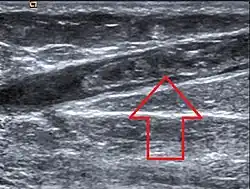

Ultrasonographic image showing thrombosis of the great saphenous vein. | |

Diagnostic method | Doppler ultrasound, Venography[1] |